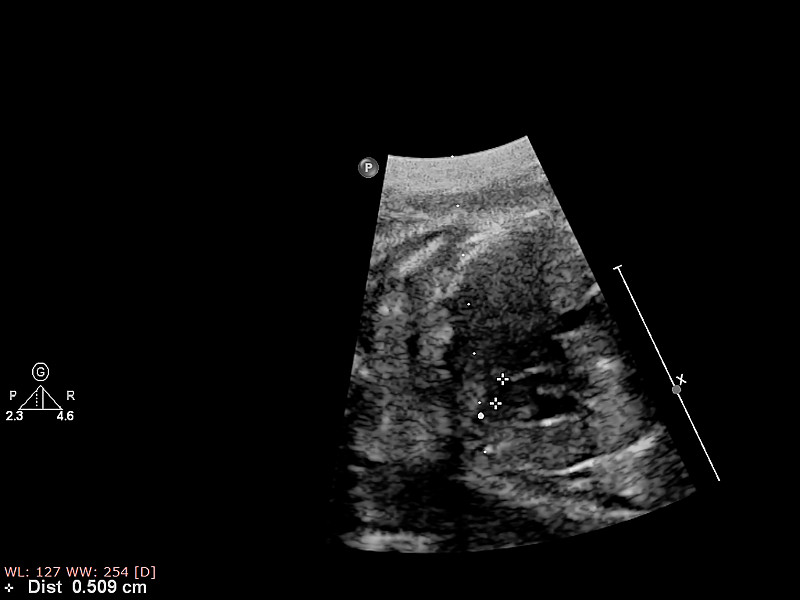

胎儿心脏的超声检查详情

胎儿心脏的超声检查详情

胎儿心脏的超声检查。详情